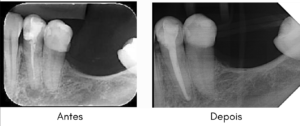

Alguns trabalhos